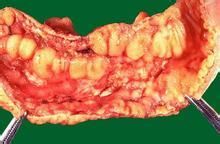

早期X線表現:腸黏膜皺襞增粗,變平及消失,病變腸段形態較固定,腸管無明顯狹窄。其它腸管可出現分節,舒張功能改變。病變進一步發展,黏膜下肉芽組織增生,黏膜可出現卵石樣或息肉樣充盈缺損,潰瘍形成。腸腔充盈時輪廓常呈鋸齒狀或尖刺狀突出。腸管固定蠕動消失。腸壁增厚,腸間距增寬。嚴重時出現不規則狹窄與穿通性、交通性潰瘍,瘺道及梗阻。

(1)腸壁的改變:腸壁增厚、壁可達1~2cm。急性期、腸壁可出現分層現象、靶征、雙暈征。內層與外層為軟組織密度環,中間為低密度環。當靜脈團注增強時,黏膜和漿膜被強化。慢性期、隨著纖維化的出現、腸壁分層消失,增強掃描時,腸壁CT值增高。(2)腸系膜改變:腸系膜肥厚,病變腸襻與正常腸襻分離,腸間距離加大。增強掃描時又可見“梳樣征”。(3)腹腔內改變:隨著病情發展,可出現腹腔膿腫、蜂窩組織炎。約20%~40%的病人會出現瘺。